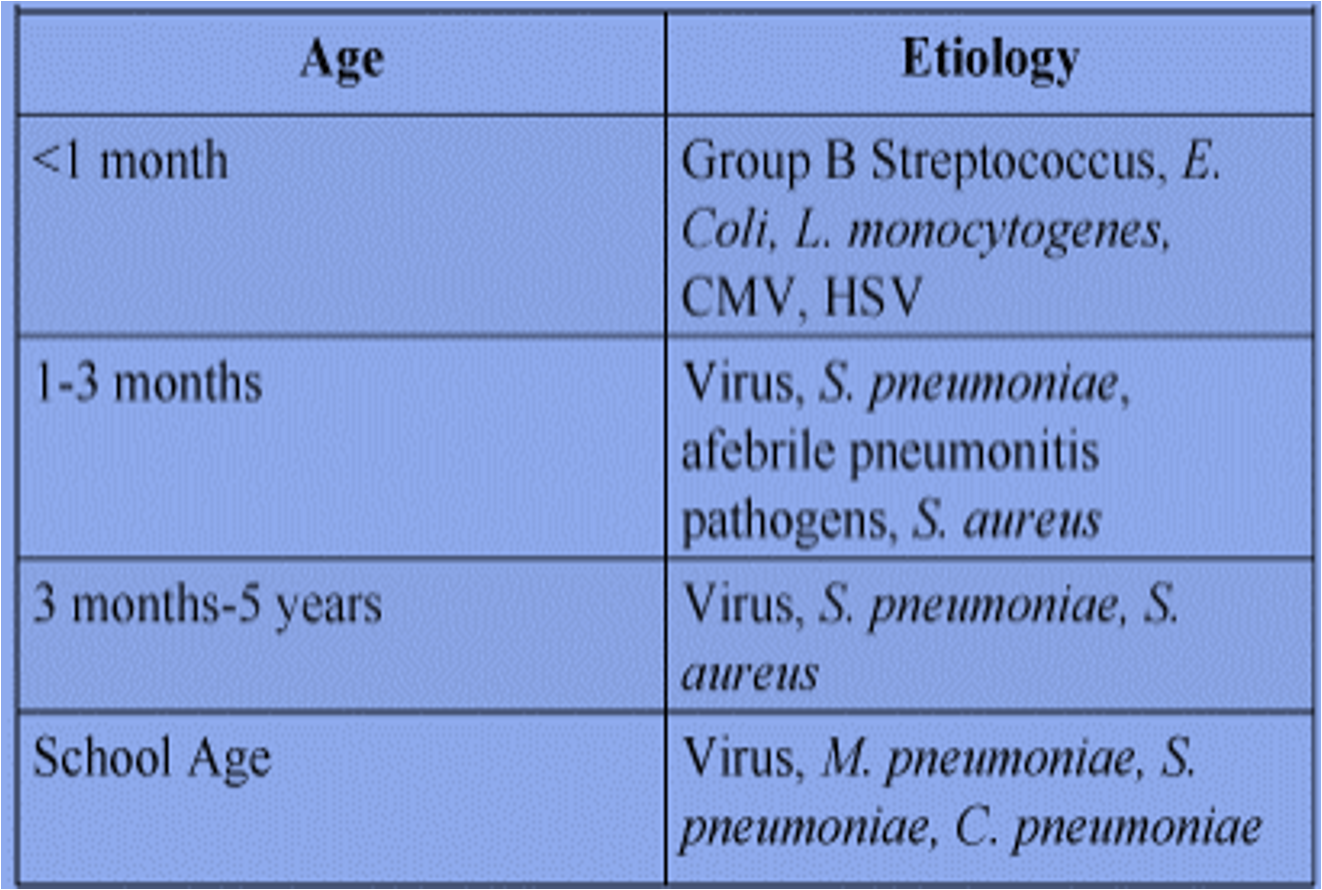

AGE SPECIFIC ETIOLOGY OF PNEUMONIA

| AGE GROUP | FREQUENT PATHOGENS (IN ORDER OF FREQUENCY) |

|---|---|

| Neonates (<3wk) | Group B streptococcus, Escherichia coli, other gram-negative bacilli, Streptococcus pneumoniae, Haemophilus influenzae (type b,* nontypeable) |

| 3wk-3mo | Respiratory syncytial virus, other respiratory viruses (rhinoviruses, parainfluenza viruses, influenza viruses, human metapneumovirus, adenovirus), enterovirus D68, S. pneumoniae, H. influenzae (type b,* nontypeable); if patient is afebrile, consider Chlamydia trachomatis |

| 4mo-4yr | Respiratory syncytial virus, other respiratory viruses (rhinoviruses, parainfluenza viruses, influenza viruses, human metapneumovirus, adenovirus), enterovirus D68, S. pneumoniae, group A streptococcus |

| ≥5yr | M. pneumoniae*, S. pneumoniae, Chlamydophila pneumoniae, H. influenzae (type b,* nontypeable), influenza viruses, adenovirus, COVID-19, other respiratory viruses, Legionella pneumophila |

* H. influenzae type b is uncommon with routine immunization.

Adapted from Kliegman RM, Jenson HJ, et al., eds. Nelson Essentials of Pediatrics, 5th ed. Philadelphia: Elsevier; 2006: p. 507.

strep p. most common